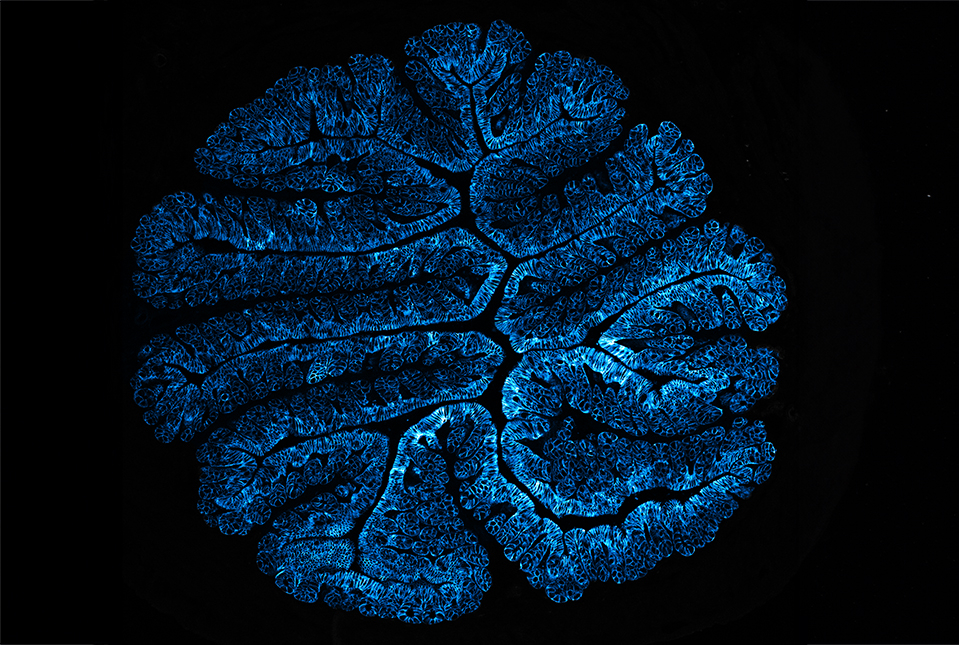

Feeding inulin to mice in the context of a model of inflammatory bowel disease increased the production of certain bile acids by specific groups of gut bacteria. The increased bile acids boosted the production of an inflammatory protein called IL-5 by ILC2s. The ILC2s also failed to produce a tissue-protecting protein called amphiregulin. In response to these changes, the immune system promotes the production of immune cells called eosinophils, which further ramp up inflammation and tissue damage. Previously, a 2022 study by the same team of investigators showed that this flood of eosinophils may help protect against parasite infections. However, in the inflammatory bowel disease model, this chain reaction exacerbated intestinal inflammation, weight loss and other symptoms like diarrhea.

In translational patient-based studies, the team also analyzed human tissue, blood and stool samples from Weill Cornell Medicine’s Jill Roberts Institute for Research in Inflammatory Bowel Disease Live Cell Bank. This analysis revealed that patients with inflammatory bowel disease, like the mice fed inulin, had higher levels of bile acids in their blood and stool and excessive levels of eosinophils in their intestine compared with people without the condition. The results suggest that the inflammation cascade similar to that in the mice fed inulin is already primed in humans with inflammatory bowel disease, and dietary uptake of inulin may further exacerbate the disease.